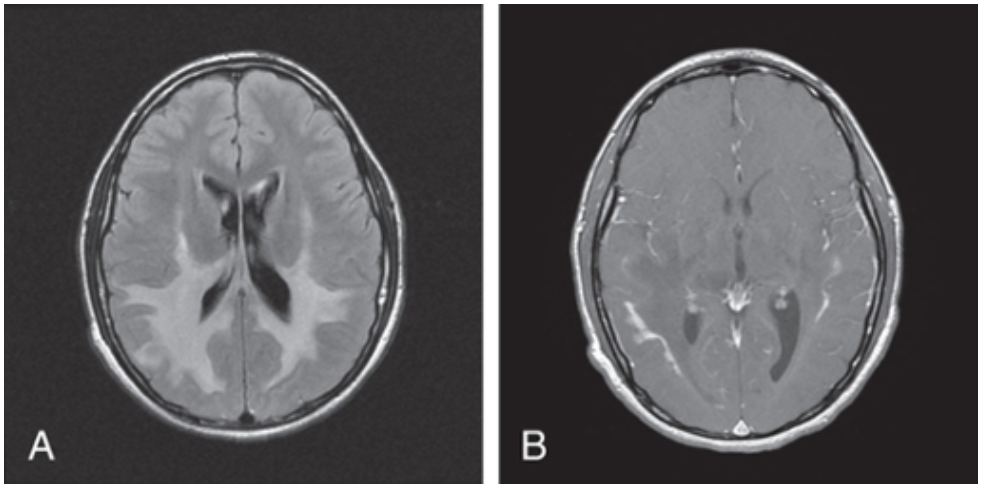

X-LINKED ADRENOLEUKODYSTROPHY

Metabolic disorder: Peroxisomal

Genetics: ABCD1 gene

Inheritance: X-linked recessive

Clinical Features: Onset 4-12yo, developmental regression (classically starting with handwriting, accompanied by behavioural deterioration [hyperactivity, ADHD]), neurologic deterioration with ataxia, seizures and paraplegia, adrenal insufficiency, impaired auditory discrimination

Investigations: Elevated VLCFAs, MRI Brain (occipital demyelination with leading edge enhancement after gadolinium administration), molecular genetic testing